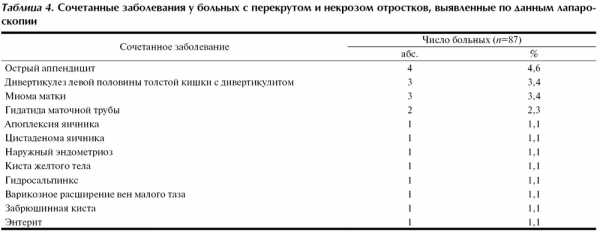

Дооперационная диагностика заболеваний отростков осложняется также возможным сочетанием перекрута и некроза отростков с другими заболеваниями органов брюшной полости и малого таза. Сочетанные заболевания по данным лапароскопического вмешательства были выявлены у 20 (23,0%) больных (табл. 4).

Сочетанное лапароскопическое вмешательство выполнено в 8 (9,2%) наблюдениях, в том числе адгезиолизис (4), удаление гидатиды маточной трубы (2), лапароскопическая аппендэктомия (2), электрокоагуляция очагов эндометриоза (1), вскрытие и коагуляция напряженной кисты желтого тела (1).